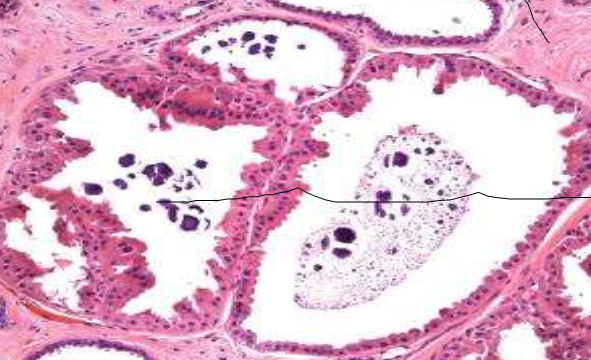

apocrine cyst morphology

large cystic areas

2 layer epithelium

apocrine metaplasia

may have calcifications